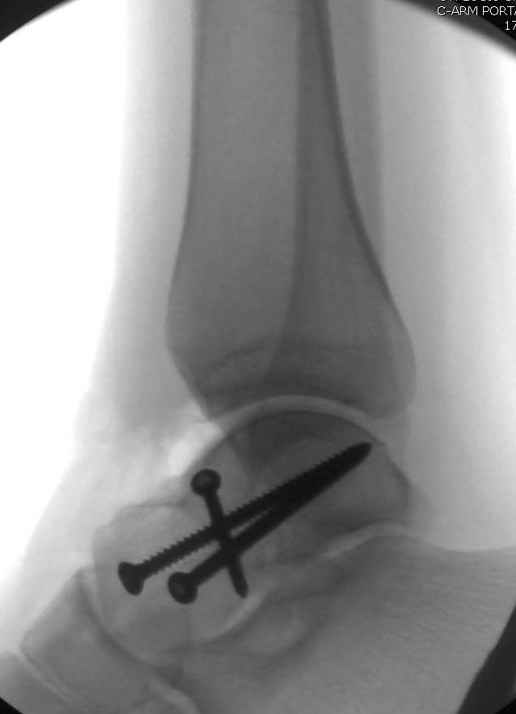

Для доступа к задне-медиальному суставному фрагменту я выполнил косую остеотомию внутренней лодыжки у её основания -получается хороший доступ к голеностопу, адекватный обзор и возможность восстановить суставную поверхность. фрагмент фиксировал двумя 3,5 мм спонгиозными винтами с неполной резьбой, *утопив* головки винтов в кость. Аналогичная фиксация и двумя тягловыми винтами и внутренней лодыжки. \в качестве альтернативы для

фиксации фрагмента тарана можно было бы использовать и герберт винты, но по организационным причинам :-(( набора не оказалось под рукой).

Вывих в таранно-ладьевидном суставе удалось вправить с помощью Howard retractor, используя его в качестве рычага.Сегодня искал в рентген архиве

послеоперационные снимки, чтобы показать, но тщётно, видимо, больной прихватил их с собой.

Повторный осмотр назначил через 2 мес с момента операции. Отдаленных наблюдений такого подхода у меня нет( достаточно редкий тип повреждений таранаHawkins II), но наблюдения в ближайшем послеоперационном периоде выглядели вполне прилично, на мой взгляд.